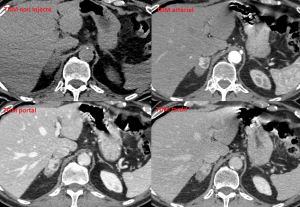

Voici les images de la TEP FDG et de la TDM sans injection puis injectée au temps artériel, portal et tardif.

-La lésion la plus antérieure correspondait en effet à un phéochromocytome : densité spontanée plus élevée, hypervasculaire (réhaussement après injection intense dès le temps artériel avec persistance au temps portal et wash-out lent au temps tardif), hypermétabolique en TEP FDG et hyperfixant en MIBG.

-La lésion plus postérieure correspondait à un adénome surrénalien typique : densité spontanée basse ( < 10 UH sur la mesure), réhaussement modéré après injection et wash-out rapide au temps tardif, pas d'hypermétabolisme en FDG ni en MIBG.

Il s'agissait donc d'un cas de "tumeur collision" avec co-existence de 2 lésions dont les caractéristiques morphologiques et fonctionnelles étaient bien distinctes.